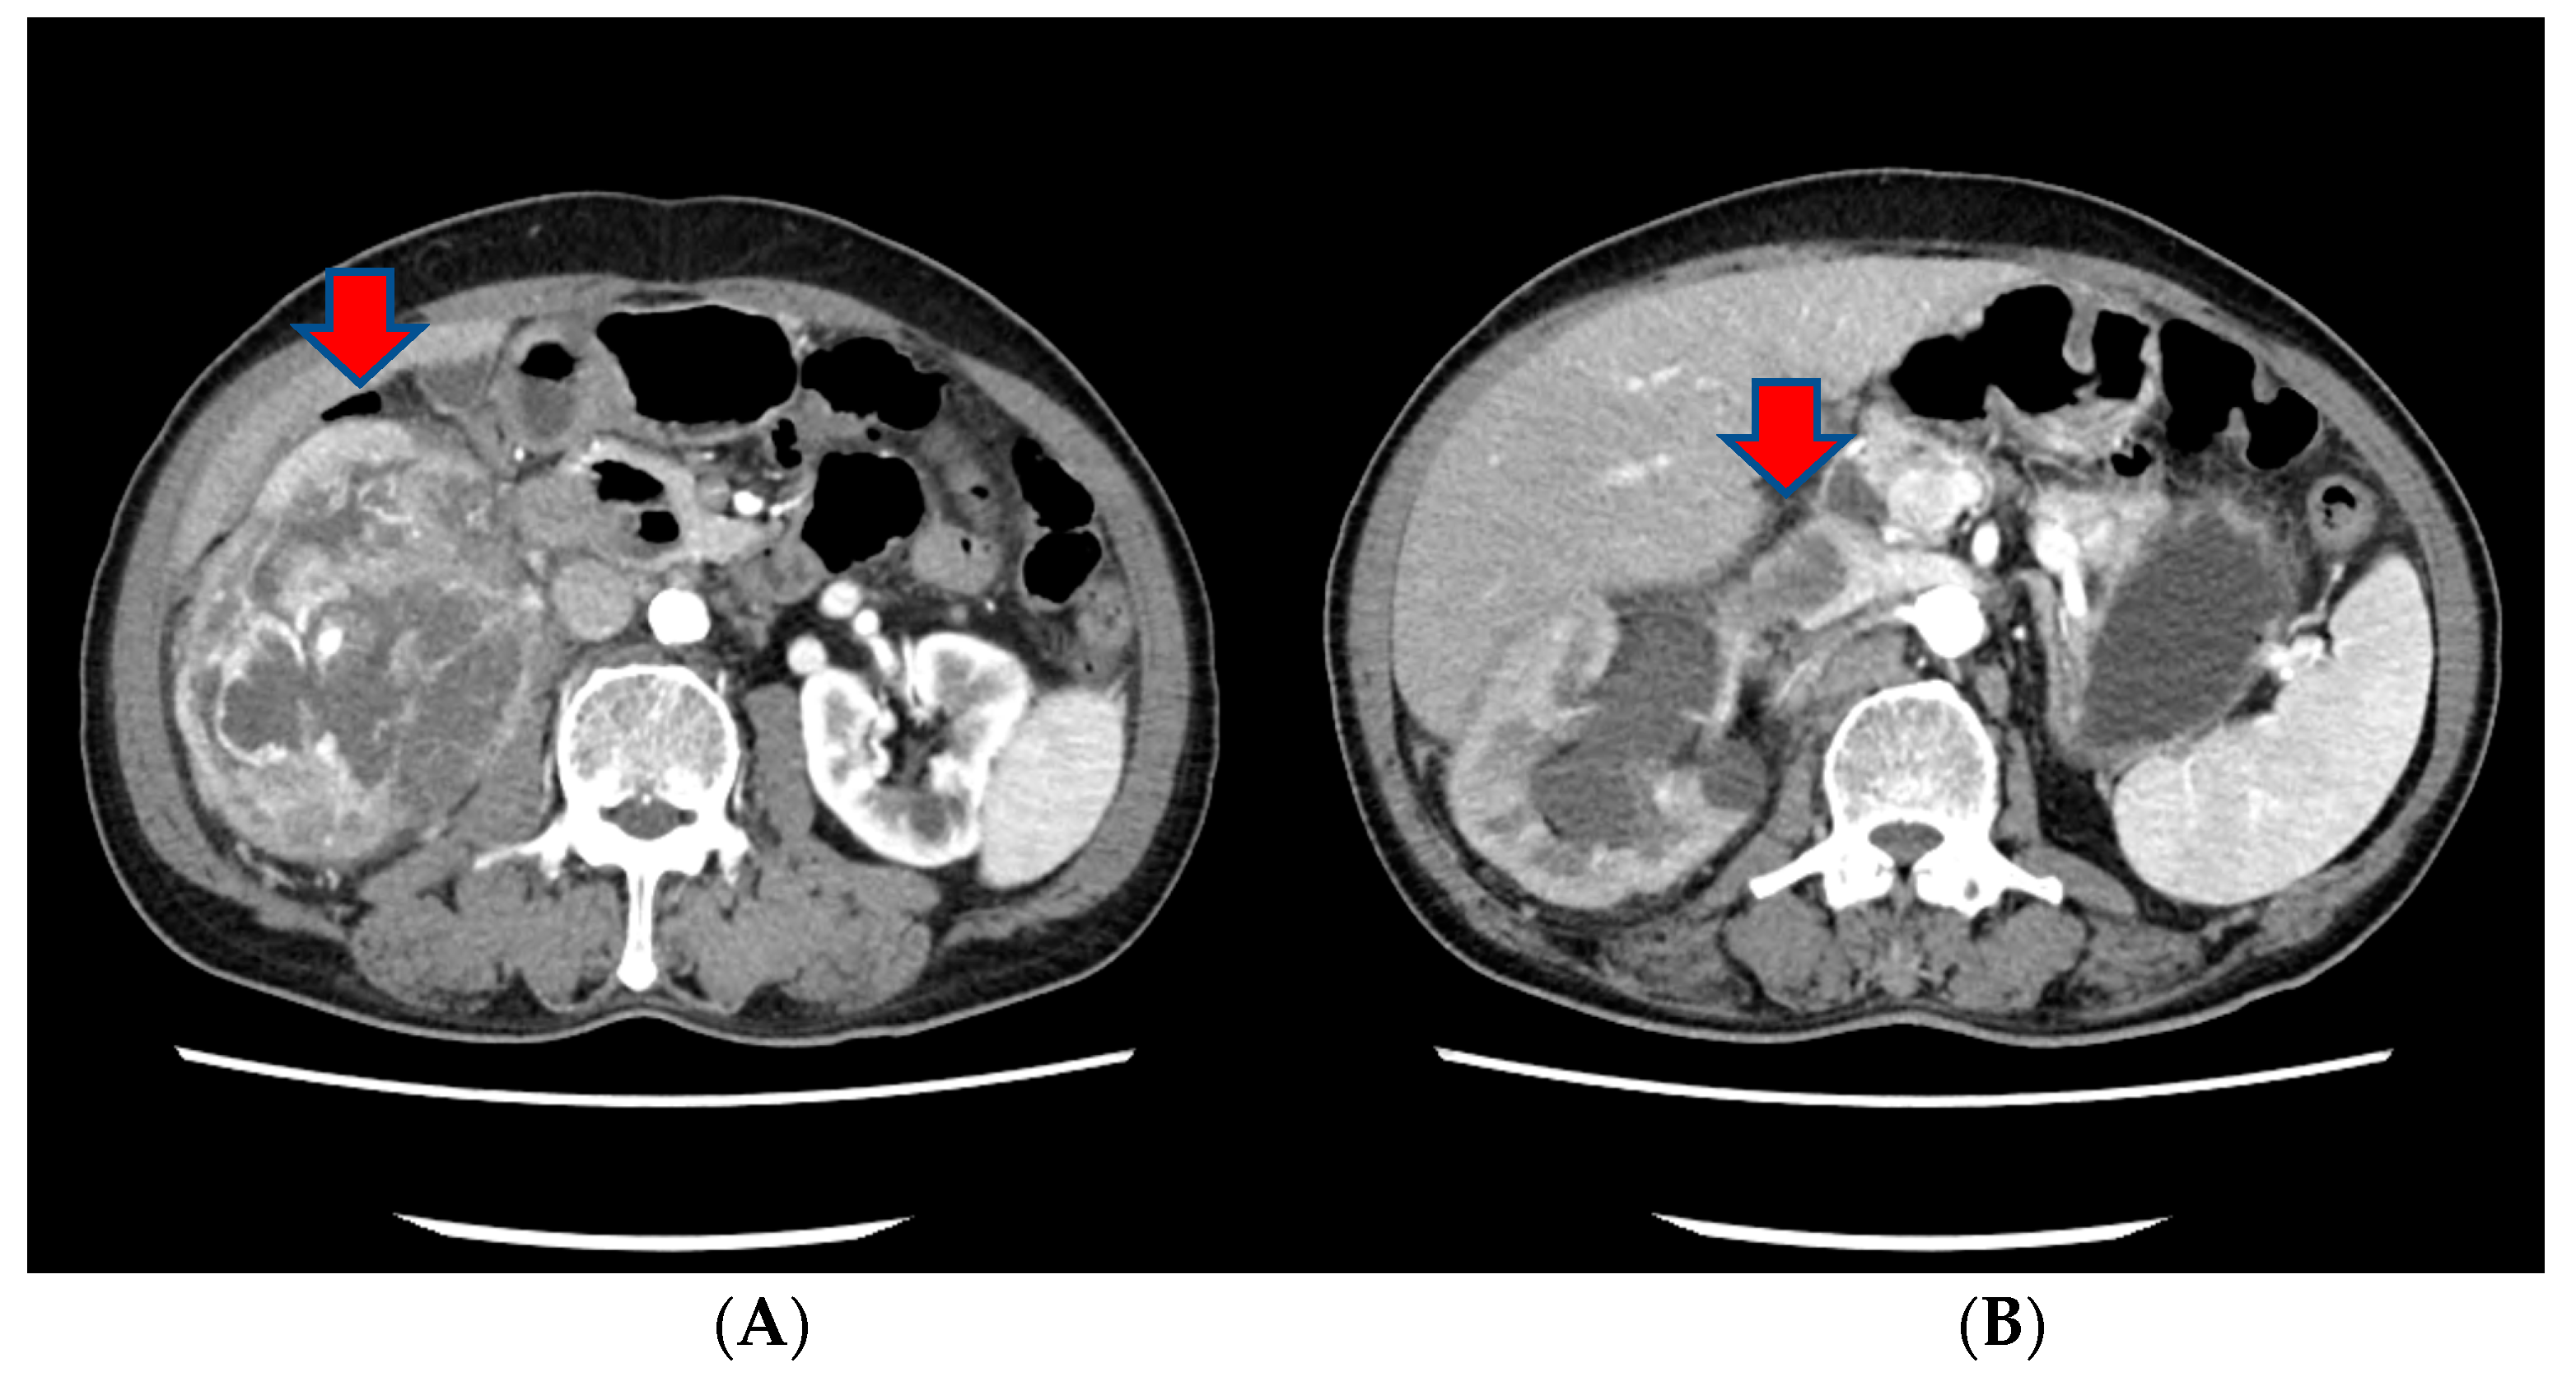

The patient underwent an open radical nephrectomy with thrombectomy and was subsequently diagnosed with clear cell RCC with tumor thrombosis in the IVC upon microscopic and immunohistochemical examination (Figure 2).

Figure 2.

The histopathological findings of the resected kidney tissue and of tumor thrombosis in the inferior vena cava. (A) A renal mass (12.5 cm at its greatest dimension) replaces nearly the entire right kidney. The cut surface is diffusely necrotic (red arrow) with frequent tumor thrombi (white circle) at large vessels (the provided scale unit is 5 mm). (B) The tumor is partly encapsulated with multiple venous tumor invasions (white circles) (HE, ×10). (C) Separately sent tissue designated ‘inferior vena cava thrombi’ was involved with tumor cells (T3) (HE, ×40). (D) The tumor cells disclose clear/oncocytic cytoplasm (clear cell renal cell carcinoma) with Fuhrman nuclear grade 3/4. (HE, ×100).